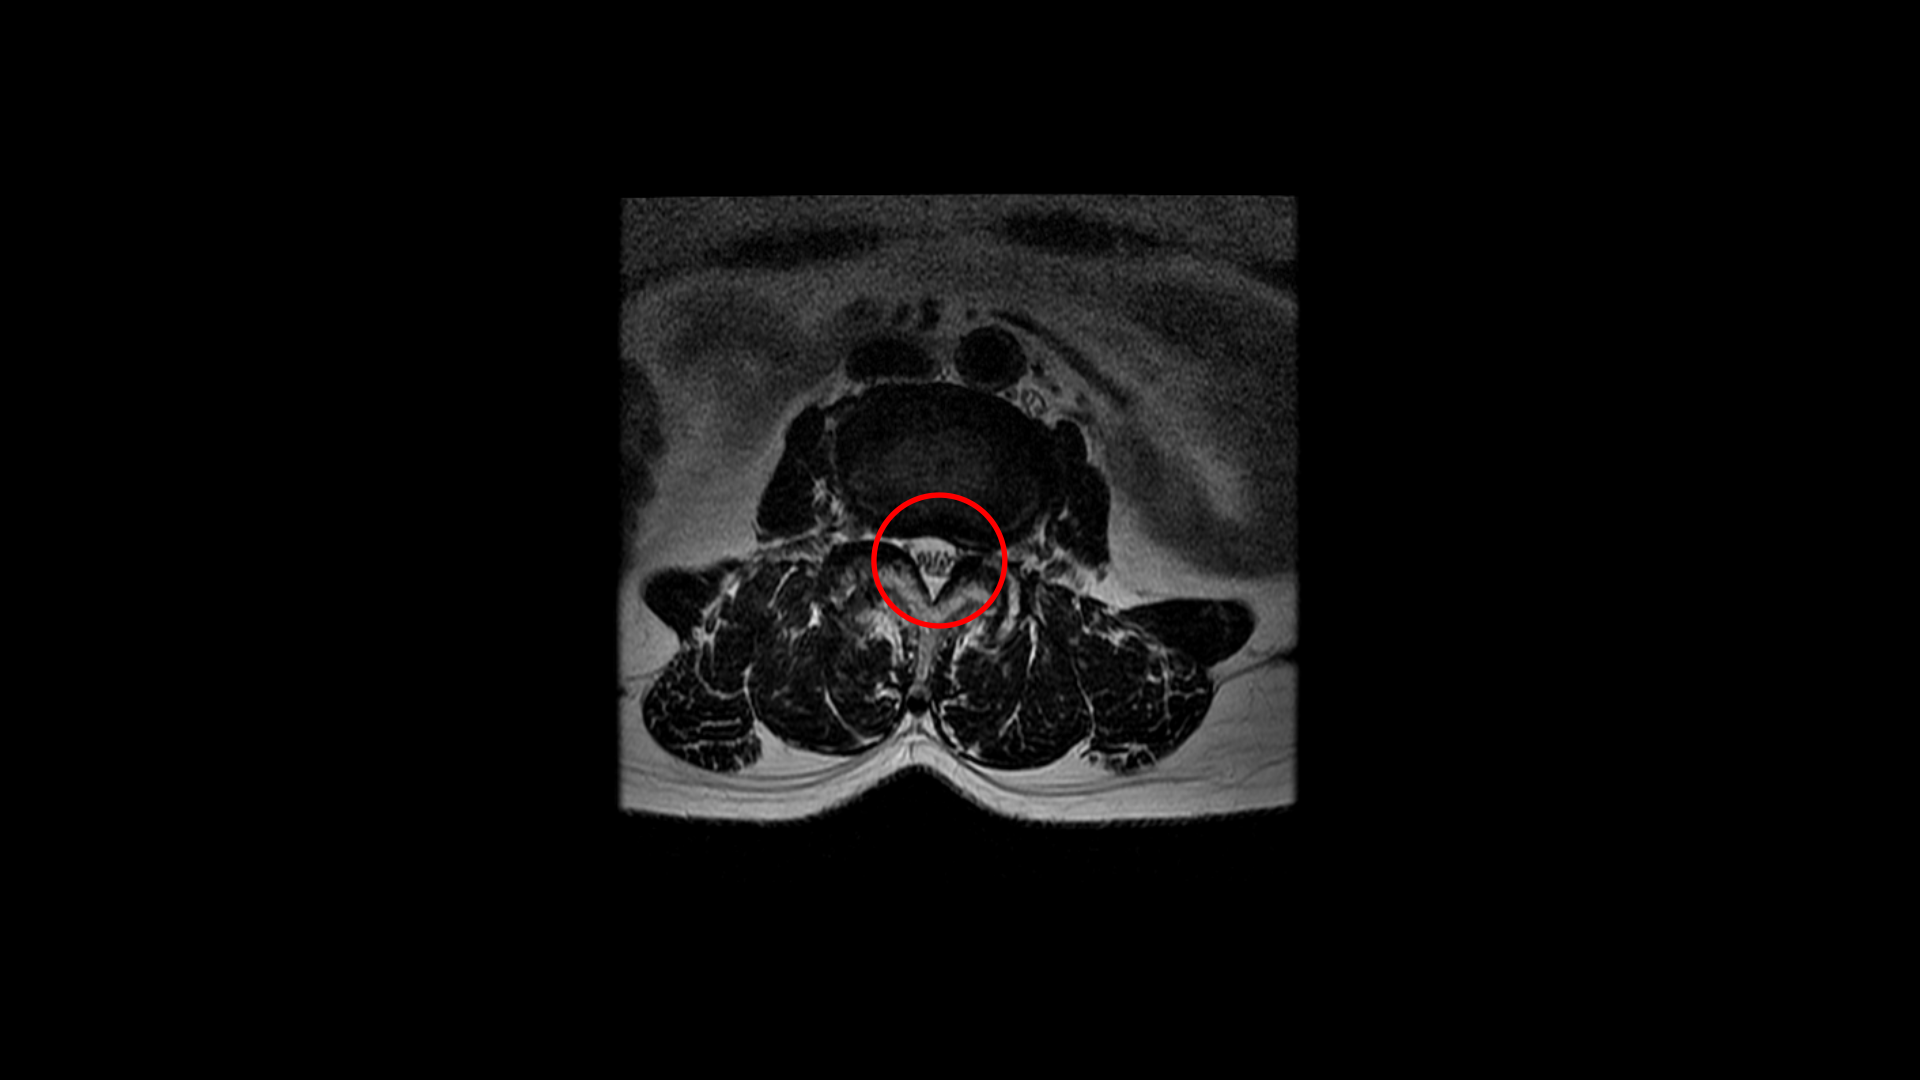

그런데 이 환자분의 제일 불편한 증상은 왼쪽이 아니고 오른쪽 엉치와 다리 증상입니다. 이분 오른쪽 신경 구멍들을 보면 전부 다 넓게 잘 열려 있습니다.

엉치와 다리 방사통을 일으킬만한 특별한 신경 눌림이 보이지 않는 것입니다. 그럼에도 불구하고 여러 마디의 전방전위증과 척추관 협착 그리고 디스크 탈출이 있으니까 그것을 원인으로 보고 신경 주사도 맞고 시술도 받으셨습니다. 그러나 별 효과는 없었습니다. 그리고 대학병원에서도 결국은 수술밖에 방법이 없다고 수술을 권유하였습니다.

이 환자분은 MRI에서 오른쪽에 신경 눌림이 심해 보이지 않는 상태에서 오른쪽에 심한 방사통과 함께 오른쪽 중둔근이 극심하게 뭉쳐있는 것이 확인되었습니다. 만일 이 근육들을 풀어서 하룻밤 사이에 방사통이 사라진다면 그건 명확히 근육성 방사통이었던 겁니다. 보통 단단하게 뭉쳐있는 근육에 의한 방사통이라해도 하루만에 치료가 되는 경우는 매우 드뭅니다. 특히 7년씩이나 방사통이 있었으면 근육이 뭉쳐도 정말 심하게 뭉쳐있을 거고 엉덩이 근육만이 아니라 허리 근육 및 다리 근육들도 다 뭉쳐있을 가능성이 높기 때문에 1-2주 정도 매일 4-5회 이상 다양한 방법으로 근육을 풀어주면서 쉬는 걸 반복하는, 즉 풀어주고 쉬고 풀어주고 쉬고 풀어주고 쉬고를 반복해야 극심하게 뭉친 근육이 풀립니다. 그래야 방사통이 사라지고 좋아지는 겁니다.